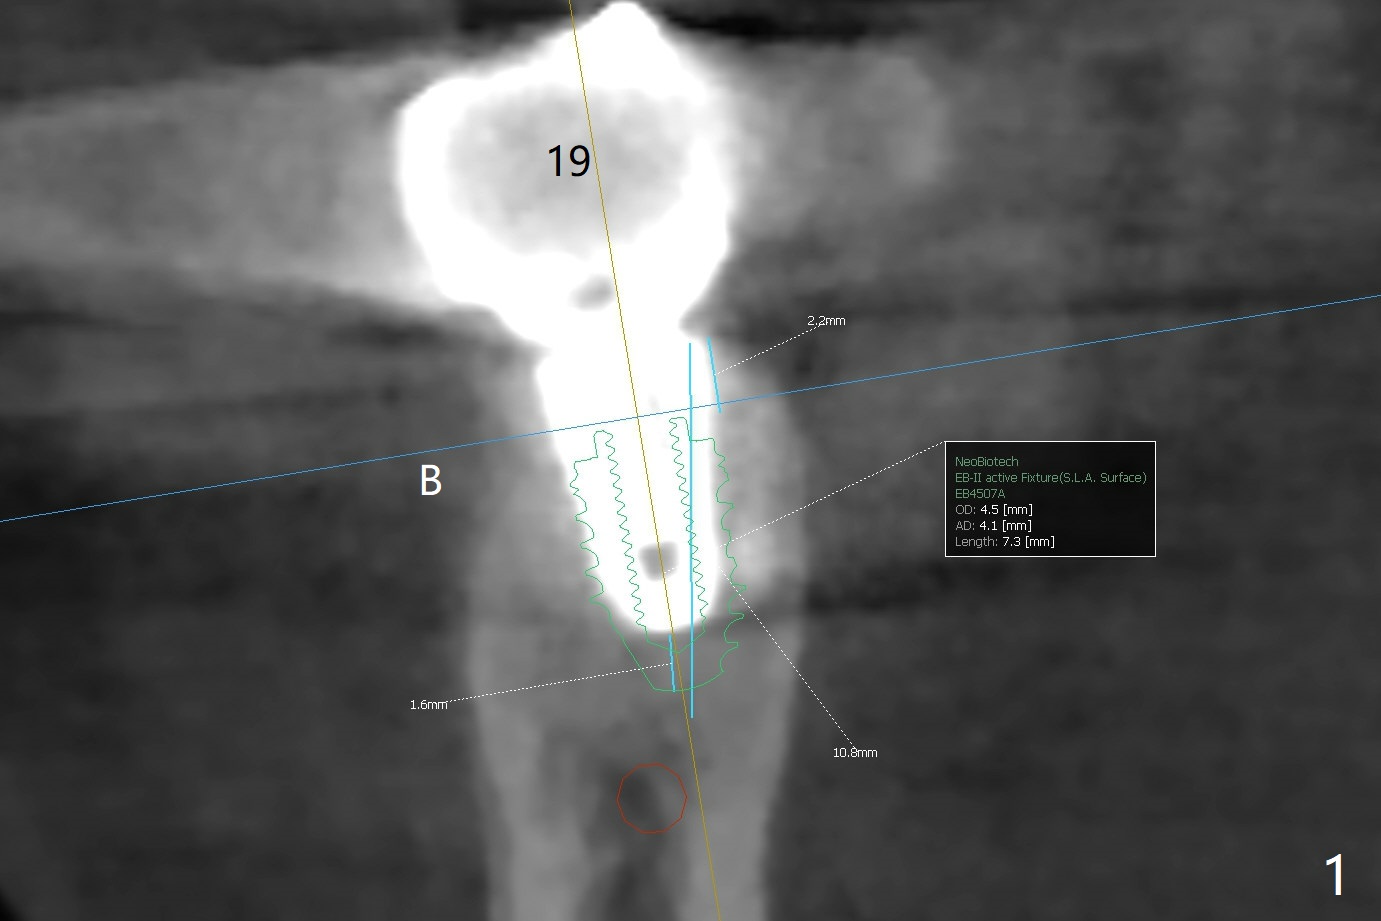

Since there is ~ 2 mm bone apical to the 5x8 mm loose implant at #19 (Fig.1), primary stability is achieved for a 4.5x10 mm dummy IS implant (having better surface treatment than the previous implant) when osteotomy is finished with a 4 mm drill (Fig.2). It is the same associated with a 4.5x7.3 mm definitive one with apical space (Fig.3 *). After depth adjustment to make sure that the implant is subcrestal circumferentially, sticky bone is placed on the top of the implant and around the implant at #18 (Fig.4 *), followed by PRF membranes and suturing with 5-0 PGA and 4-0 Chromic gut suture. Periodontal dressing is applied around the cemented abutment at #18 for additional retention. There is no paresthesia postop. In fact immediate implant redo is fairly safe. The wound heals 1 month postop (Fig.5). There is reorganized bone coronal to the healing screw 4 months postop (Fig.6), which is confirmed in uncovering. One month post uncover, the 6x4 mm healing abutment is found to be loose, suggesting incomplete seating after uncover. A 5.2x4.5(4) mm cemented abutment seems to be incompletely seated (Fig.7). It remains the same after 5.5 and 6.0 mm profile drills (Fig.8,9). A 4.5x4.5(4) mm abutment appears to be completely seated (Fig.10). When the crowns of #18 and 19 are cemented, the gingival embrasure between them is narrow (Fig.11 ^) because of bulky porcelain build-up (*). The tooth #21 with buccal Class V defect (Fig.12 *) seems to have occlusal trauma 1 year 6 months post cementation of #18 and 19. The problems are subsequently taken care of.